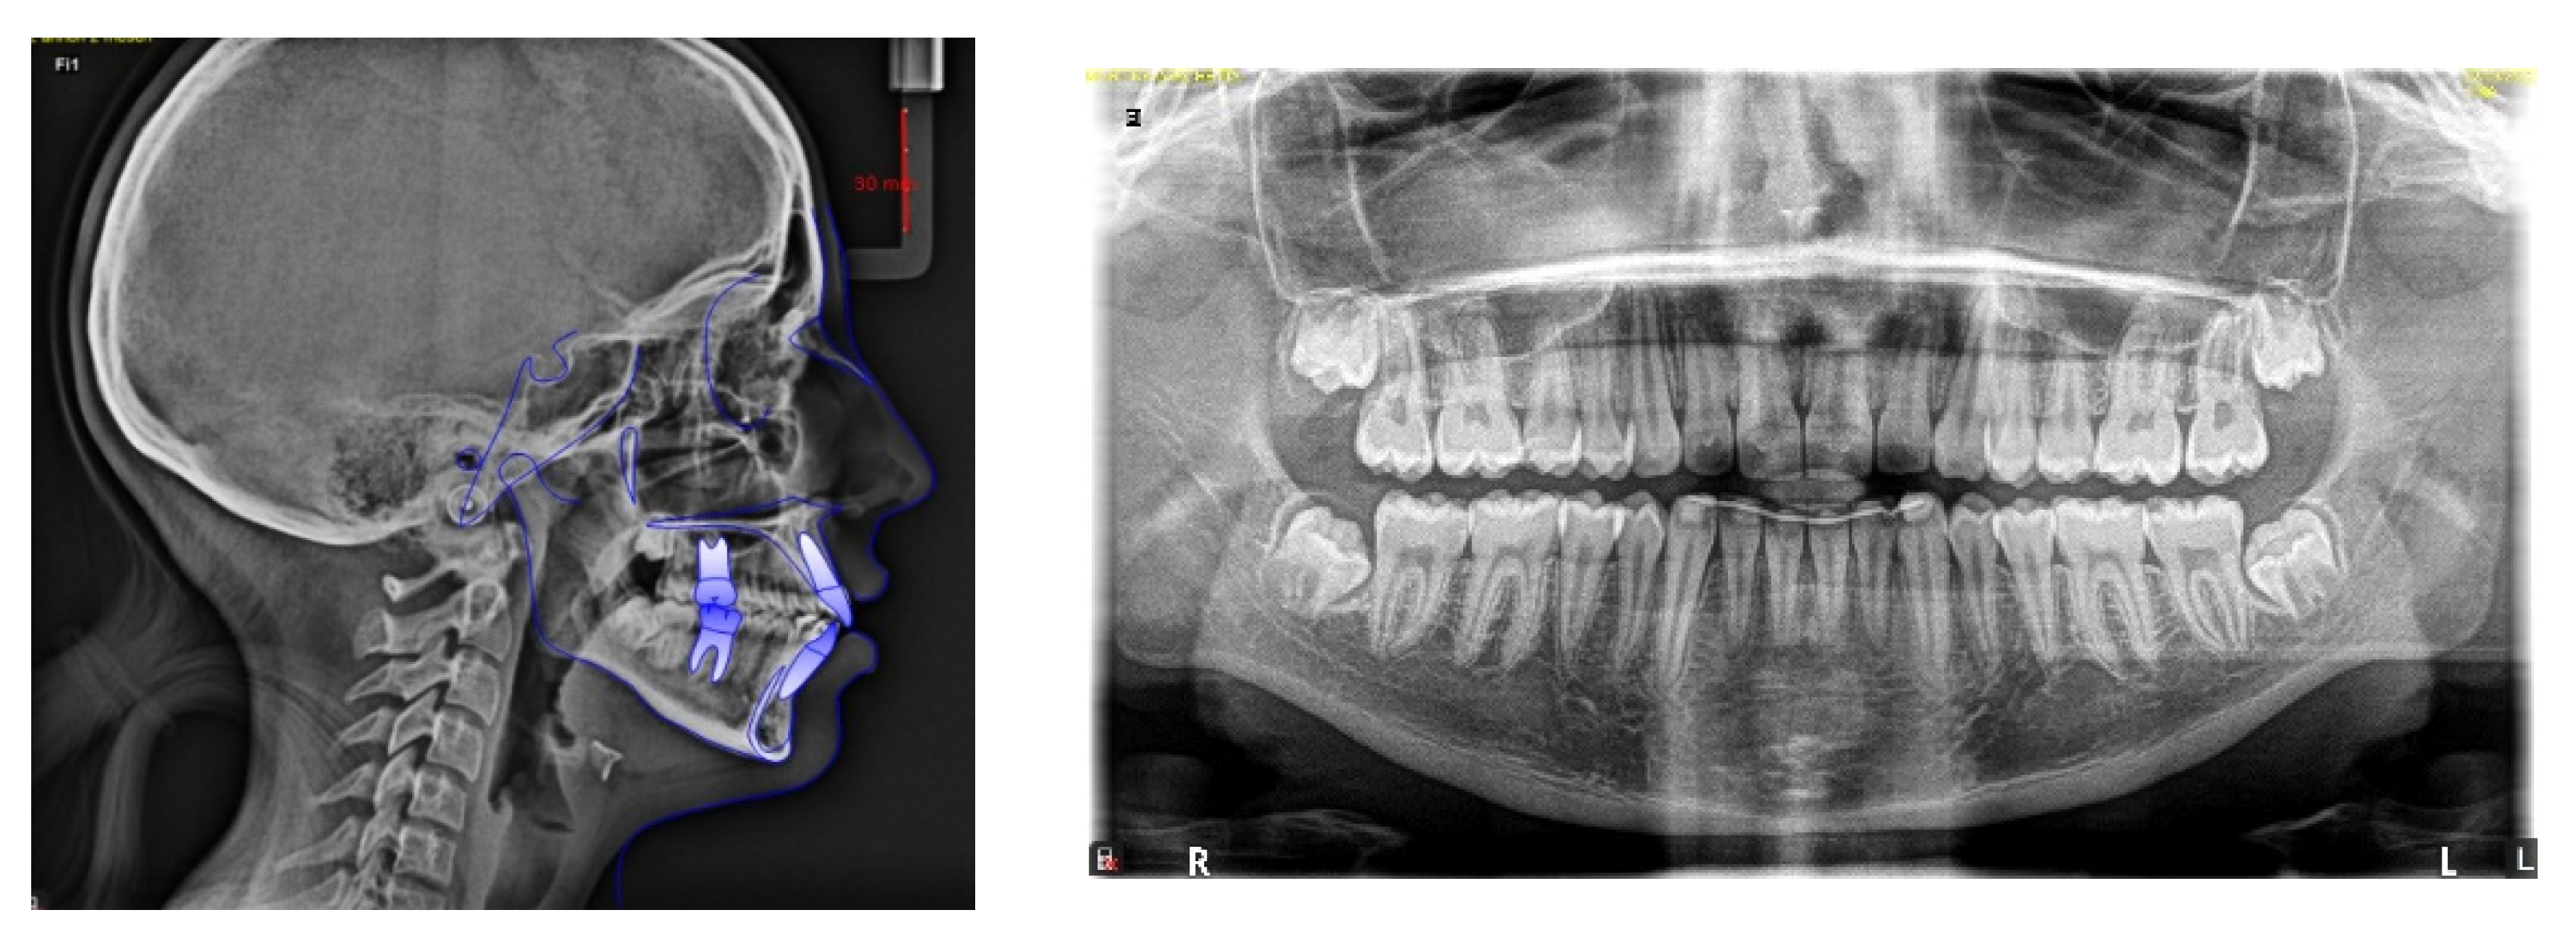

4. Case Report

4.1. Etiology and Diagnosis

4.2. Treatment Objectives

4.3. Treatment Strategy

4.4. Treatment Progress